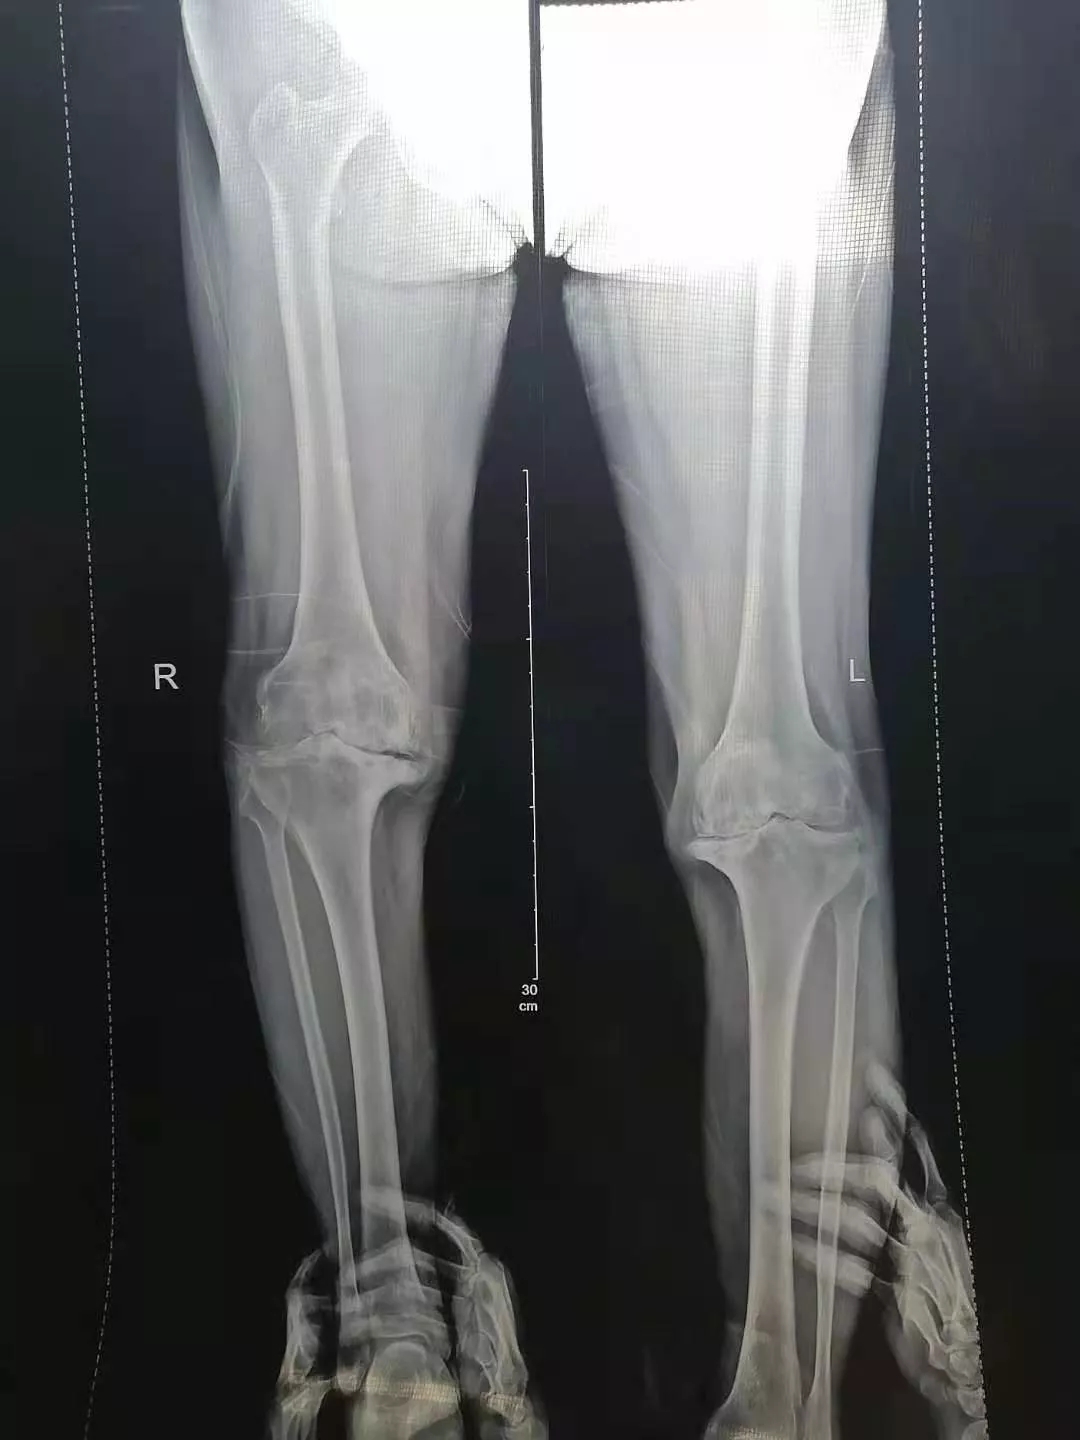

患 者:女,76岁。

主 诉:双侧膝关节疼痛10余年,伴渐进性加重的畸形和活动受限。曾长期行不规范的保守治疗。

查 体:左膝活动范围20°~40°,HSS评分35分;右膝活动范围25°~40°,HSS评分30分。

检 查:术前负重位X-ray显示双膝重度骨性关节炎合并屈曲内翻畸形。

术前影像:

术前正位

术前侧位